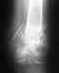

Верятно, то, что использовали другой стержень, было обусловлено тем, что во время операции купленный не подошел по размеру. Но сделано все неплохо и с этим стержнем.

Вам уже с месяц пора ходить с полной нагрузкой, т.е. без трости и костылей. Это так?

Если гвоздь был заперт статически, также уже пора его отпереть, убрав один винт вверху - это сделано?

Если сращение не наступит через 2-3 мес. после динамизации гвоздя и ходьбы с полной нагрузкой (это крайне редко, но бывает), оптимально будет заменить стержень на другой, большего диаметра. Как правило, это решает проблему.